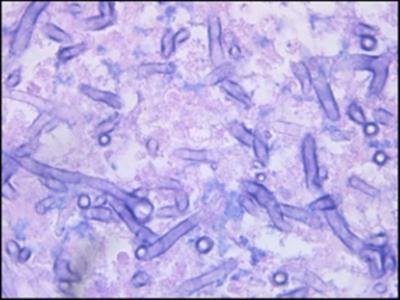

ही बुरशी कोठे आढळते? म्युकोरमायकोसिससंदर्भात बोलताना एका पत्रकार परिषदेत डॉ. गुलेरिया म्हणाले, म्युकोरमायसीट्स नामक तंतुमय बुरशीचे तंतू म्युकोरमायकोसिसला कारणीभूत ठरतात. ते हवेत, मातीत, आणि अगदी अन्नातही आढळतात. हवेतील कवकधारी कनांच्या माध्यमातून ते शरीरात शिरकाव करू शकतात किंवा त्वचेला कापणे/भाजणे, अशी दुखापत झाली असल्यास ते त्वचेवरही आढळतात. या संसर्गाचे वेळेवर निदान झाल्यास, संभाव्य अंधत्व किंवा मेंदूचा संसर्ग टाळता येऊ शकतो.

खरे तर, अशा प्रकारचा संसर्ग कोरोना पूर्वीही आढळून येत असे. मात्र, त्याचे प्रमाण अत्यंत कमी होते. मात्र, आता कोरोनामुळे हा संसर्ग मोठ्या प्रमाणावर फोफावताना दिसत आहे. कोरोना मधून बरे होत असलेल्या किंवा झालेल्या रुग्णांमध्ये सीएएम म्हणजे कोरोनाविषाणू रोगाशी संबंधित म्युकोरमायकोसिस होत असल्याचे आढळून आले आहे.

कोरोनाबाधितांना म्युकोरमायकोसिसचा अधिक धोका का? कोरोनावर उपचार करताना वापरलेल्या औषधांमुळे लिंफोसाइट्स म्हणजे प्रतिकारशक्तीचा घटक असणाऱ्या श्वेतपेशींची संख्या कमी होण्याची शक्यता असते. श्वेतपेशींचे तीन प्रकार असतात, त्यापैकी एक प्रकार रोगकारक जीवांपासून- जीवाणू, विषाणू, व परजीवी यांपासून शरीराचे रक्षण करतो. या पेशी कमी झाल्यामुळे लिंफोपेनिया स्थिती उद्भवते आणि यामुळे बुरशीजन्य संसर्गाला कोविड-19 रुग्णाच्या शरीरात शिरकाव करण्याची संधी मिळते. महत्वाचे म्हणजे, ज्या रुग्णांची रोगप्रतिकारशक्ती व्यवस्थित काम करू शकत नाही, अशा लोकांना म्युकोरमायकोसिसची लागण होण्याची शक्यता अधिक असते.